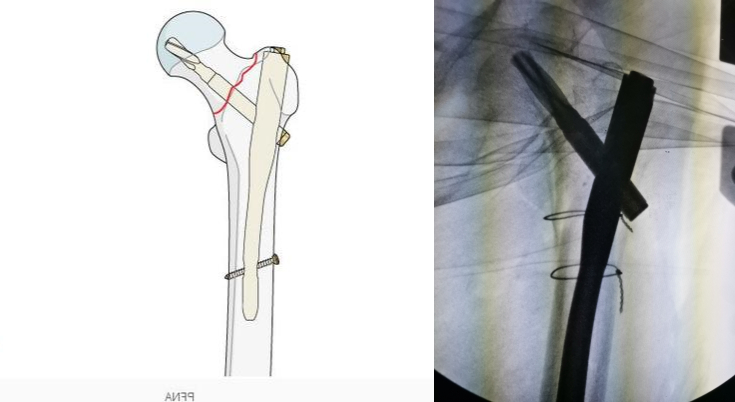

在完全复位后就可以进行髓内钉内固定的操作,我们将髓内钉插入骨髓腔,对骨折断端进行固定:

髓内钉

髓内钉的优势如下:

- 髓内钉相比较钢板螺钉是中心性固定,不易断裂,可以早期下床活动,术后第二天就可以扶助行器行走,利于早期康复锻炼;

- 髓内钉较人工关节不易出现脱位等术后并发症,术中创伤小,利于恢复。

熟练的髓内钉内固定操作手术时间在30分钟左右,显性出血量在50ml以内,因此,该手术对患者机体的影响不大,已有百岁以上老人行此类手术报道,术后恢复满意。正因为该手术创伤小,术后可早期下床活动,相比较卧床风险而言收益大,越来越多的医生会推荐积极手术治疗。由于有些老人身体条件差或者骨折粉碎严重,即便不能下床行走,也可床边坐立,可以有效避免卧床并发症。